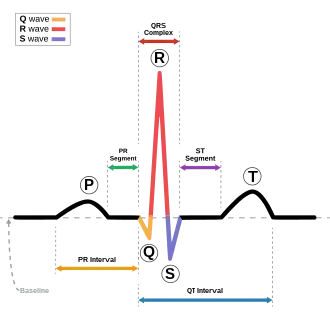

The QRS complex is the combination of three of the graphical deflections seen on a typical electrocardiogram (ECG or EKG). It is usually the central and most visually obvious part of the tracing. It corresponds to the depolarization of the right and left ventricles of the heart and contraction of the large ventricular muscles.

In adults, the QRS complex normally lasts 80 to 100 ms; in children it may be shorter. The Q, R, and S waves occur in rapid succession, do not all appear in all leads, and reflect a single event and thus are usually considered together. A Q wave is any downward deflection immediately following the P wave. An R wave follows as an upward deflection, and the S wave is any downward deflection after the R wave. The T wave follows the S wave, and in some cases, an additional U wave follows the T wave.

To measure the QRS interval start at the end of the PR interval (or beginning of the Q wave) to the end of the S wave. Normally this interval is 0.08 to 0.10 seconds. When the duration is longer it is considered a wide QRS complex.

Ventricles contain more muscle mass than the atria. Therefore, the QRS complex is considerably larger than the P wave. The QRS complex is often used to determine the axis of the electrocardiogram, although it is also possible to determine a separate P wave axis.